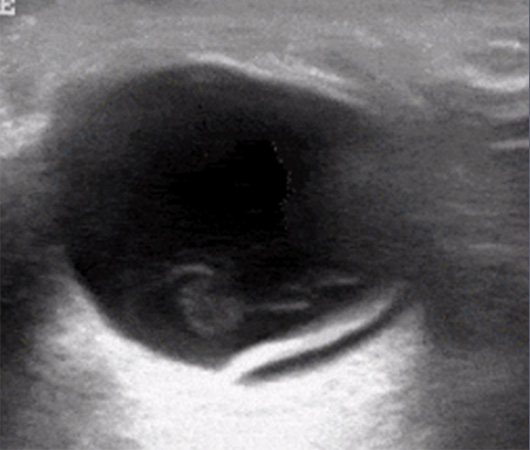

Retinal detachment

- Retinal detachment